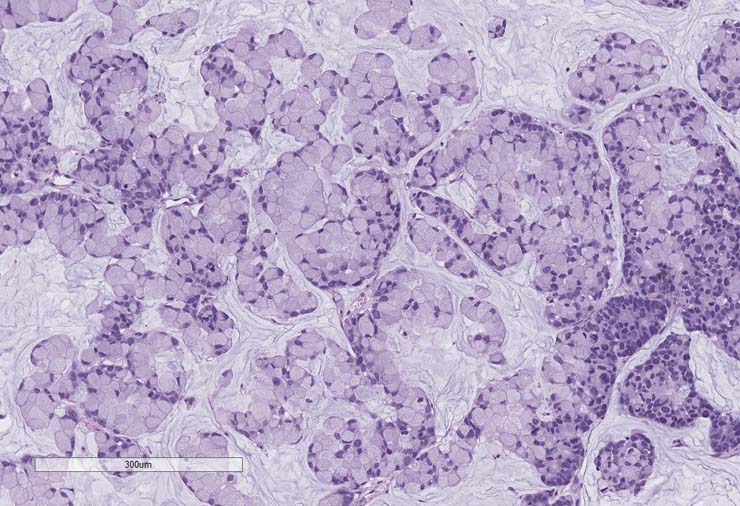

P0 tumor F240 for PDX model TM00351 stained for AE1AE3. Staining was positive.

P1 tumor F239 ID003 for PDX model TM00351 stained for AE1AE3. Staining was positive.

P2 tumor F239 ID011 for PDX model TM00351 stained for AE1/AE3. Staining was positive.